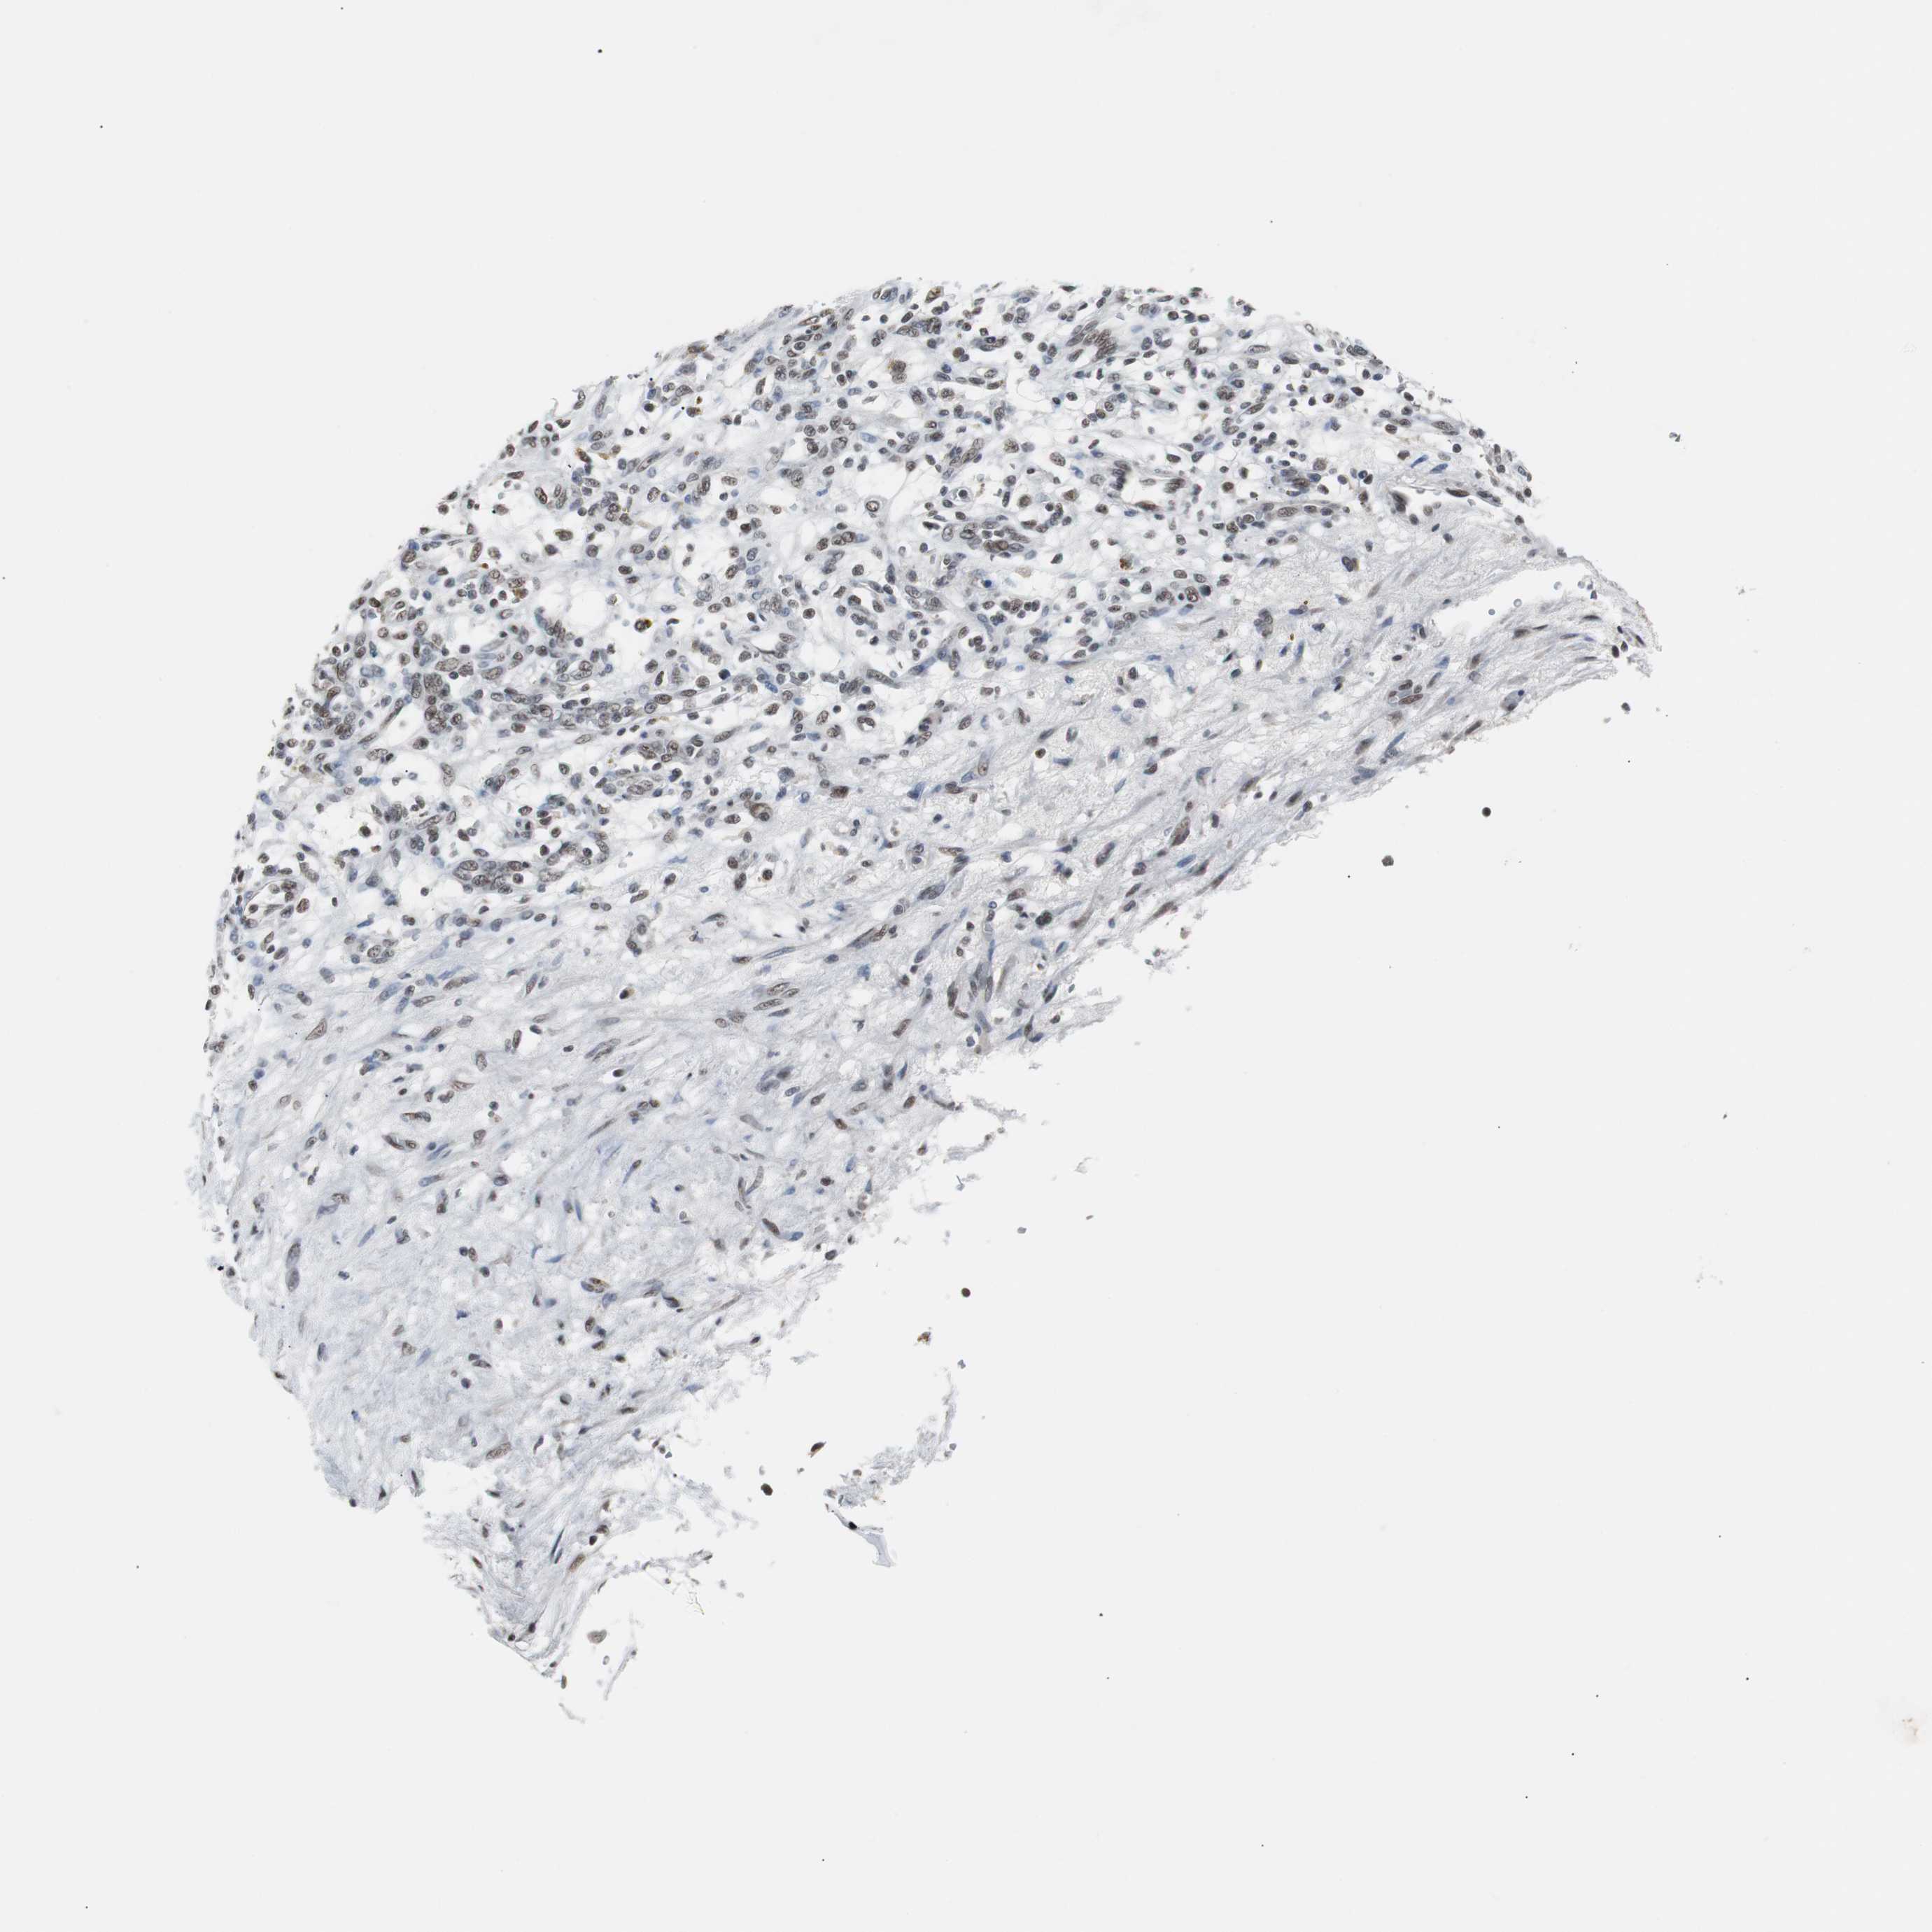

KIDNEY RENAL PAPILLARY CELL CARCINOMA (TCGA) - Interactive survival scatter ploti

The Survival Scatter plot shows the clinical status (i.e. dead or alive) for all individuals in the patient cohort, based on the same data that underlies the corresponding Kaplan-Meier plots. Patients that are alive at last time for follow-up are shown in blue and patients who have died during the study are shown in red.

The x-axis shows the expression levels (FPKM) of the investigated gene in the tumor tissue at the time of diagnosis. The y-axis shows the follow-up time after diagnosis (years). Both axes are complimented with kernel density curves demonstrating the data density over the axes. The top density plot shows the expression levels (FPKM) distribution among dead (red) and alive patients (blue). The right density plot shows the data density of the survived years of dead patients with high and low expression levels respectively, stratified using the cutoff indicated by the vertical dashed line through the Survival Scatter plot. This cutoff is automatically defined based on the FPKM cutoff that minimizes the p-score. The cutoff can be changed by dragging the vertical line or by entering a cutoff value in the square labeled "Current cut-off".

Under the Survival Scatter plot the p-score landscape (black curve; left axis) is shown together with dead median separation (red curve; right axis). Dead median separation is the difference in median mRNA expression between patients who have died with high and low expression, respectively. It is calculated as follows: median FPKM expression of dead patients with high expression - median FPKM expression of dead patients with low expression. This is intended to aid the user in visually exploring custom cutoffs and the associated p-scores and dead median separation.

Individual patient data is displayed and can be filtered by clicking on one or more of the category buttons on the top of the page. Categories describing expression level and patient information include: high, low, alive, dead, female, male and tumor stages. The scale of the x-axis can be toggled between linear and log-scale by clicking on the "x log" button. Mouse-over function shows TCGA ID, patient information and mRNA expression (FPKM) for each patient.

& Survival analysisi

Kaplan-Meier plots summarize results from analysis of correlation between mRNA expression level and patient survival. Patients were divided based on level of expression into one of the two groups "low" (under cut off) or "high" (over cut off). X-axis shows time for survival (years) and y-axis shows the probability of survival, where 1.0 corresponds to 100 percent.

TAF7 is not prognostic in Kidney Renal Papillary Cell Carcinoma (TCGA)